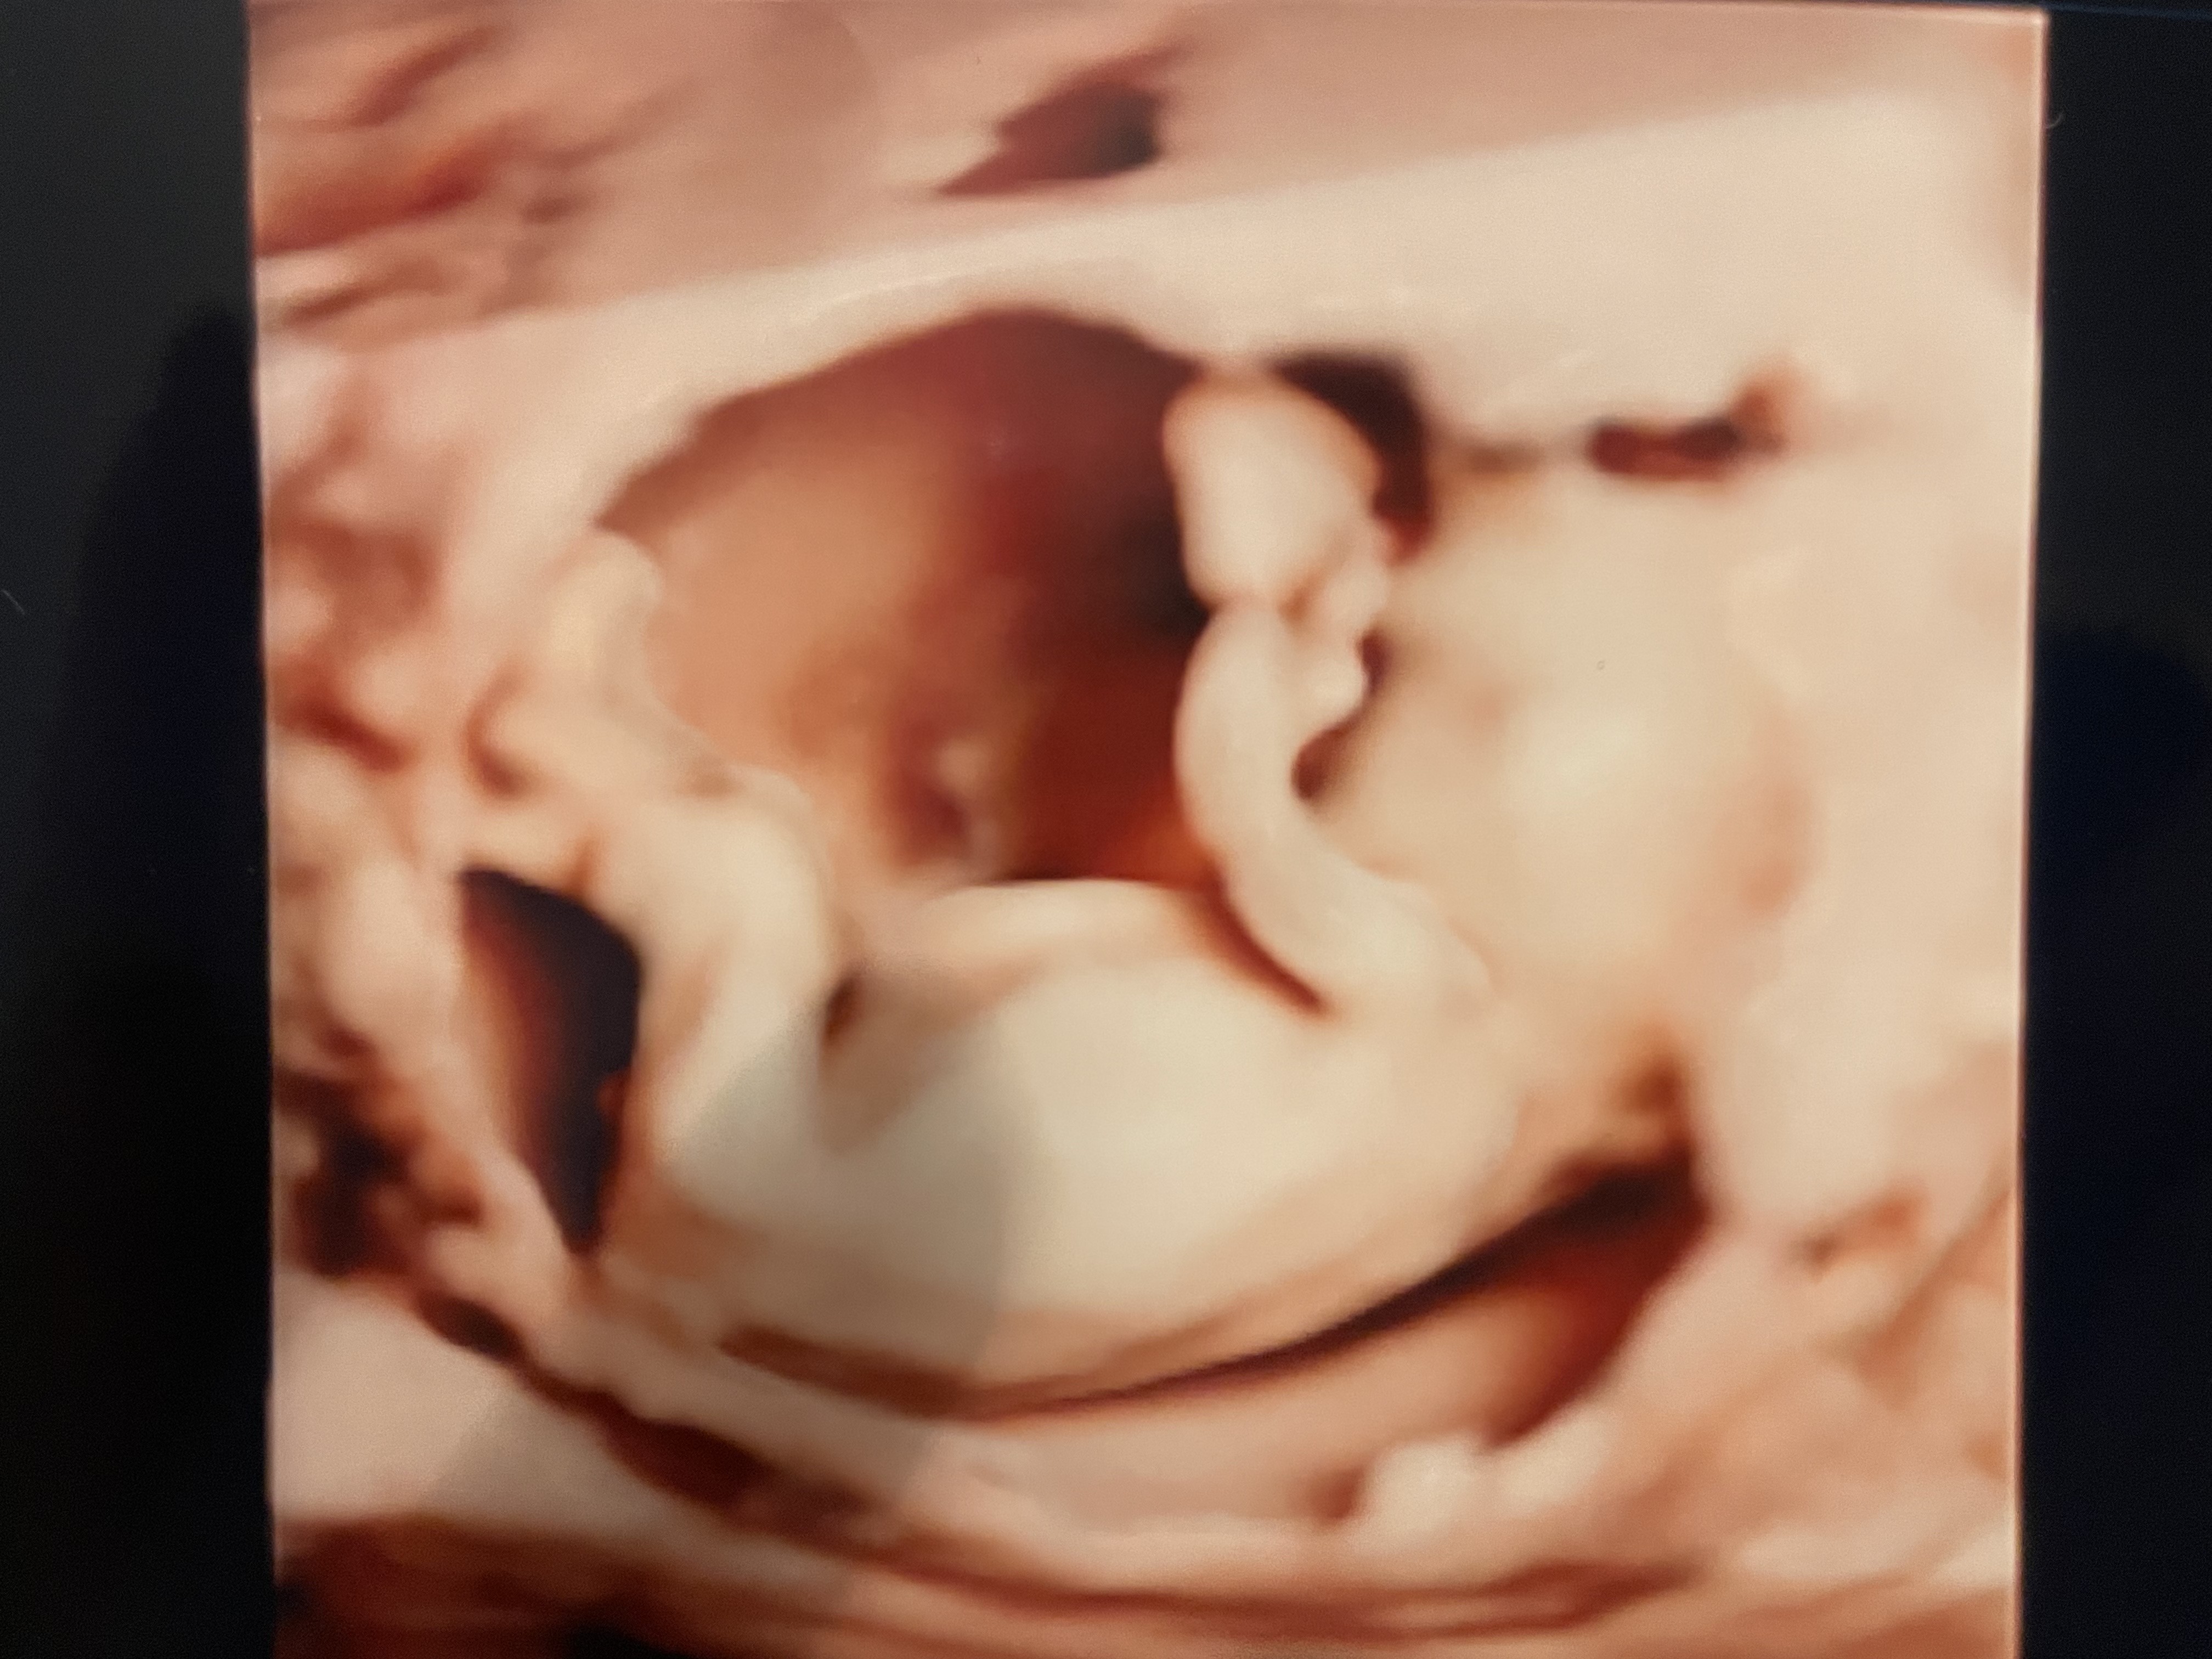

Cześć Dziewczyny, bardzo Was przepraszam, ale miałam dziś taki dzień, ze jeszcze nie dotarłam do domu! Już Wam wszystko opisze o moich badaniach prenatalnych. Po pierwsze byłam na takich prywatnych badaniach, które sprawdzają nie tylko podstawowe trisomnie i wady genetyczne, ale analizują całe dziecko anatomicznie od głowy do stop. U mnie wszystko jest super. Głupio mi o tym pisać w kontekście tego, co wydarzyło się dziś u Pszczółki, ale mam nadzieje ze da to Wam wszystkim nadzieje. Moja córka - okazało się ze to dziewczyna

- rośnie jak na drożdżach i znowu jest większa niż zakładany tydzień z ostatniego usg- aktualnie ma wymiary na 14 tydzień i był to ostatni moment na badanie 1. Trymestru. Termin porodu tez na ten moment przesunął mi się na 28 czerwca, ale mam nadzieje ze nie wydalicie mnie z grupy, bo się z Wami zżyłam :-) Lekarz sprawdził przepływy dziecka w wątrobie, sercu i mózg, pokazał wszystkie narządy, pomierzył bardzo dużo rzeczy i opisał wynik na 2 strony stwierdzając, ze jest wszystko super! Powiedział tez, jeśli chodzi o badania z krwi pappa, ze to jest tylko badanie pomocnicze i absolutnie nie jest ani miarodajne ani do końca wiarygodne i nie należy do niego przywiązywać wagi (co ponoć robi się na Fundusz, bo taka jest procedura, stad tak wiele biopsji kosmowki, gdzie wszystko wychodzi ok). Dostałam zdjęcia i dostałam film z nagraniem całego przebiegu badania z analiza tych wszystkich organów. Zapłaciłam za wizytę 400 zł i uważam, ze były to super wydane pieniądze. Jak ktoś jest z Krakowa lub okolic to mogę polecić z czystym sumieniem to miejsce :-) choć sam profesor jest specyficzny w odbiorze i kontakcie, ale jest mega specem od usg płodów :-) spróbuje Wam zaraz podłączyć jakaś fotkę :-) i jak macie jakieś pytania to piszcie!